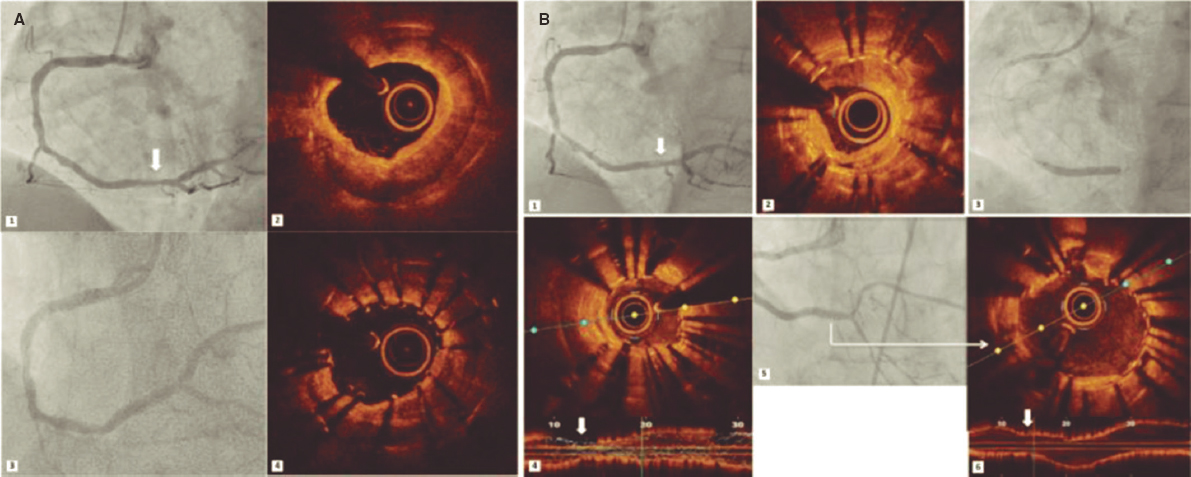

An 84-year-old female with severe aortic stenosis and previous non-disabling stroke was referred to undergo transcatheter aortic valve replacement (TAVR). The 3D computed tomography performed revealed the presence of a type 9 aortic arch with severe tortuosity (figure 1A). It was decided to protect the supra-aortic branches with suitable diameters to be able to use the Sentinel Cerebral Protection System (Boston Scientific, Marlborough, MA, United States). Manipulation length in the left common carotid artery (LCCA) was of, at least, 8 cm which is the distance between the proximal filter and the Sentinel distal edge. Figure 1B: yellow arrow: brachiocephalic trunk, 12 mm-diameter. White arrow: LCCA, 7 mm-diameter. This cerebral protection device (CPD) has a proximal filter for brachiocephalic trunk diameters between 9.0 mm and 15 mm and a distal filter for LCCA diameters between 6.5 mm and 10 mm. The angiography of the aortic arch is shown on figure 1C. This dual-system-filter basket was tried unsuccessfuly over a 0.014 in guidewire despite the use of an articulating sheath (figure 1D-F). After several attempts, a multipurpose catheter was used to engage the LCCA (figure 1G). Using a 300 cm 0.014 in guidewire, the multipurpose catheter was exchanged for the CPD which allowed its suitable deployment (figures 1H,I). The TAVR was performed successfully and the CPD was retrieved (video 1 of the supplementary data). Informed consent was obtained from the patient.

Figure 1.

The major concern is how to balance the risk of stroke after TAVR and the risk of manipulation with guidewires/catheters in supra-aortic arteries. Thus, the rigorous study of the computed tomography scan is the key factor for strategic planning purposes. This was an alternative approach to achieve the placement of a Sentinel device using a multipurpose catheter in a complex aortic arch.